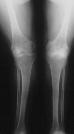

was a limited community ambulator with the following knee x-rays with definite

knee valgus and recurvatum in stance phase.